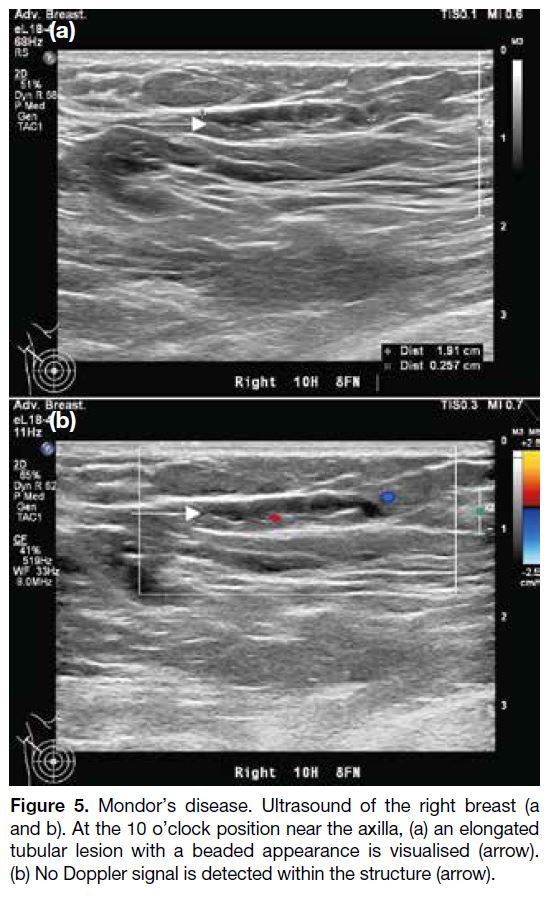

On ultrasound, Mondor’s disease is seen as a tubular

a dilated duct which usually with smooth wall (Figure 5).[6] It is also longer in extent and will not be connected

Figure 5. Mondor’s disease. Ultrasound of the right breast (a and

b). At the 10 o’clock position near the axilla, (a) an elongated tubular

lesion with a beaded appearance is visualised (arrow). (b) No

Doppler signal is detected within the structure (arrow).